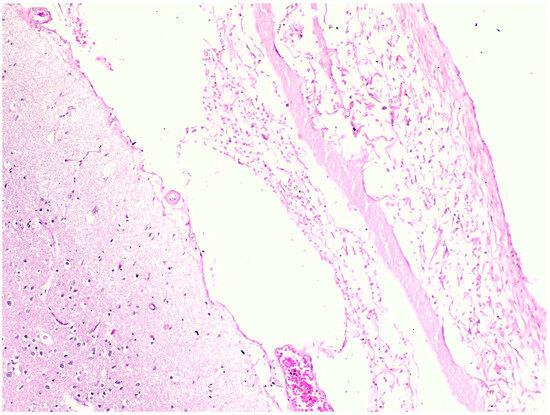

3.2. Microscopic Histopathological Findings

| 1 | N/A | Hemorrhage at subendocardial and myocardium | Edema | Steatosis | N/A | Partial autolysis | Partial autolysis | N/A |

| 2 | N/A | N/A | N/A | Steatosis | N/A | N/A | N/A | N/A |

| 3 | Subarachnoid congestion, hemorrhage, eosinophilic neurons | Thrombosis, myocardial necrosis, focal subendocardial hemorrhage, atherosclerosis | Diffuse alveolar damage, fibrin platelet thrombi | Multifocal ballooning degeneration (hepatocyte), steatosis | Congestion | Acute tubular necrosis, fibrin platelet thrombi in glomeruli | Focal cortical necrosis | Mucosal infarct, hemorrhage |

| 4 | N/A | N/A | Edema, congestion, petechial hemorrhage | Steatosis | Congestion | N/A | N/A | Mucosal hemorrhage, esophagitis |

| 5 | N/A | Atherosclerosis | Diffuse alveolar damage, hemorrhage, fibrosis | Cholestasis | N/A | Acute kidney injury | N/A | N/A |

| 6 | N/A | Myocardial infarction, coronary occlusion | Edema, congestion, petechial hemorrhage | N/A | N/A | N/A | Lipid depletion | Mucosal infarct, hemorrhage |

| 7 | Red blood cells within the subarachnoid space | Cardiomegaly, hemorrhage at myocardium | Edema, congestion, | Steatosis | Congestion | N/A | Lipid depletion of cortical cells | Superficial mucosal hemorrhage |